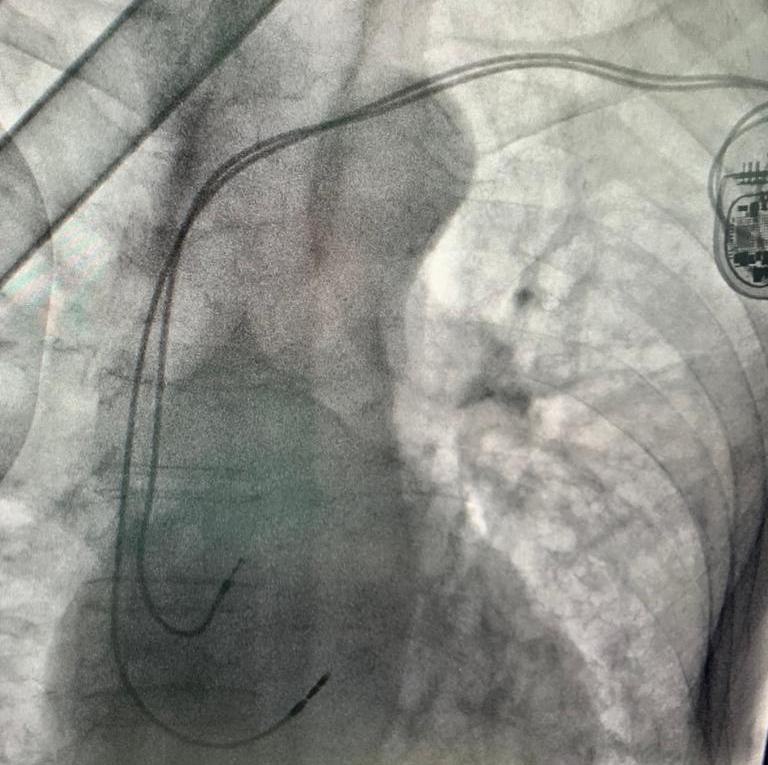

Venerdì 13 maggio 2022 presso l’ospedale regionale U. Parini è stato eseguito, per la prima volta in Valle d’Aosta, un intervento di impianto pace maker con stimolazione del fascio di His. La procedura è stata eseguita su due pazienti valdostani che presentavano un blocco cardiaco avanzato sintomatico.

La peculiarità dell’intervento consiste nella collocazione del catetere ventricolare selettivamente nel fascio di His – spiega il direttore della Sc Cardiologia, dott. Paolo Scacciatella – che è una struttura anatomica millimetrica responsabile della conduzione dello stimolo elettrico al tessuto muscolare cardiaco. Questa procedura, nota da tempo ma mai completamente realizzata per le difficoltà tecniche insite nella stessa, negli ultimissimi anni è stata riproposta e sviluppata nei principali Centri di riferimento italiani per l’Elettrofisiologia, grazie allo sviluppo di sistemi di introduzione dei cateteri di nuova generazione che ne agevolano l’esecuzione.

Questo tipo di stimolazione cardiaca, rispetto alla stimolazione tradizionale del ventricolo destro, consente di effettuare una stimolazione assolutamente fisiologica, non dissimile dalla normale attivazione del sistema elettrico del ventricolo del cuore di una persona sana. Il vantaggio di una stimolazione fisiologica è la contrazione sincrona di tutti i segmenti cardiaci, rispetto alla contrazione asimmetrica indotta dalla stimolazione tradizionale, che rimane comunque una procedura salvavita in molte condizioni cliniche”.